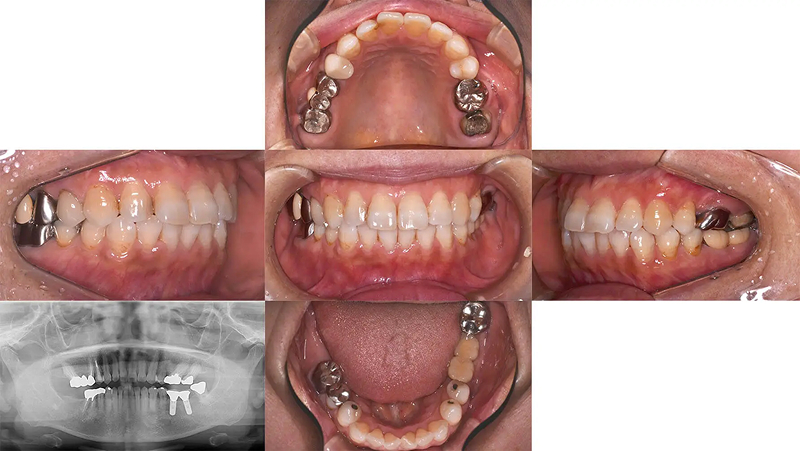

Case03部分矯正とインプラントで歯列を整えた症例

メインテナンスに通っていた患者さんであるとき、左上第2大臼歯のかぶせ物が脱離して来院されました。第2大臼歯は歯根破折をしており、残念ながら予後不良で抜歯と診断しました。元々、第2小臼歯が欠損しており、第1大臼歯がそのスペースに倒れこんでいる歯列不正がありました。この機会に歯列を整えて、インプラントをしましょうと提案しました。承諾していただき、5か月の部分矯正後、インプラントを埋入しました。3年経ちましたが経過は順調です。

初診 2016.1.21

左上7番 歯根破折 ⇒ 抜歯 左上6番 部分矯正開始 2016.2.8

左上6番 部分矯正終了 2016.7.12 ファイナル 2016.9.27

治療後3年 2019.10.12

| 主訴 | 左上1番奥歯の冠が外れた |

|---|---|

| 診断 | 右側アングル1級、左側アングル2級の叢生 |

| 矯正方法 | 矯正用アンカーを用いた部分矯正 |

| 矯正期間 | 5か月・7回 |

| 費用 | 129,000円(税別) |

| 調整料 | 月1回 5,000円(税別) |